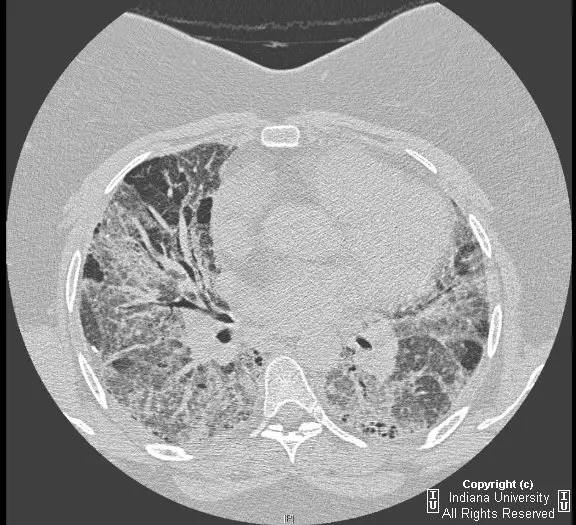

【影像学表现】胸片示双肺纹理增多,间质性透光度减低。无局灶性病变,气胸或胸腔积液。心脏及纵膈轮廓正常。CT示双肺弥漫间质性病变,累及所有肺叶,以下叶为著。肺间质增厚,结构扭曲,牵拉性支气管扩张,外周呈蜂窝状改变。肺动脉增粗,符合肺动脉高压。